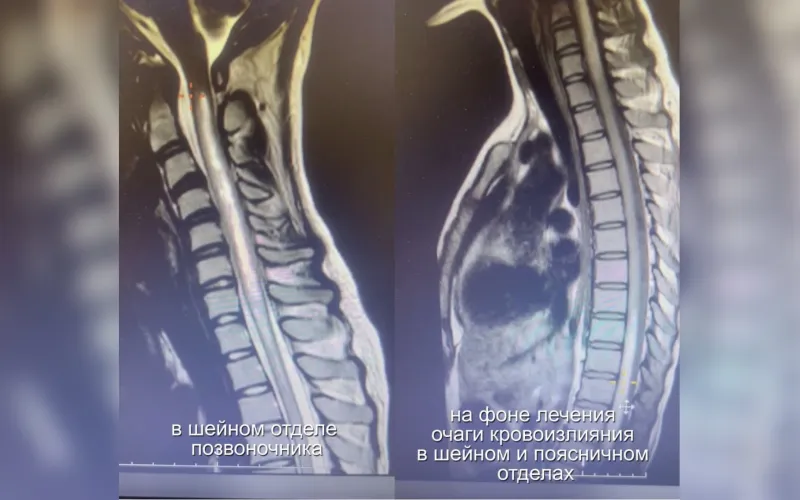

Боролись за каждое движение: барнаульские врачи спасли 18-летнюю девушку с редким поражением спинного мозга